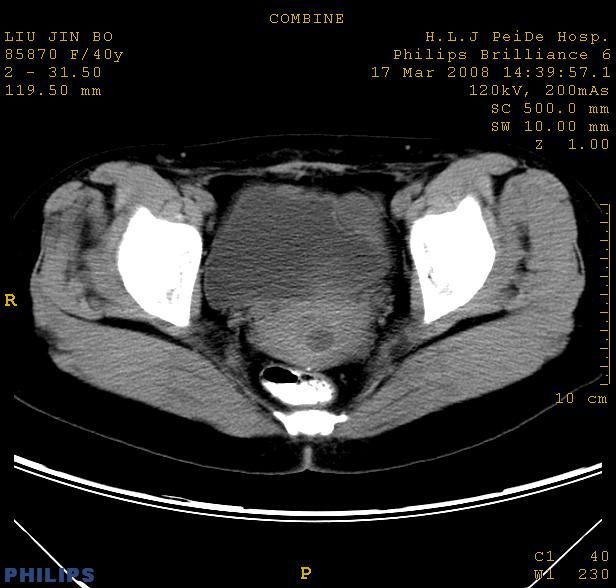

以下是引用qiuleiyu在2008-4-27 12:36:00的发言:[br]支持;右侧腰大肌后方神经源性肿瘤可能大,神经节细胞瘤?

以下是引用形影不离在2008-4-27 14:11:00的发言:[br]1.考虑右侧腰大肌脓肿。[br]2.左侧附件区炎症。[br]3.子宫增大,建议:进一步检查。